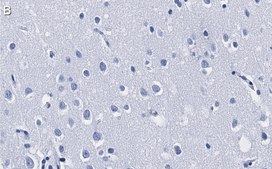

Immunohistochemistry (Paraffin) Analysis: A 1:100 dilution from a representative lot detected HDAC3 in human cerebral cortex tissue sections.